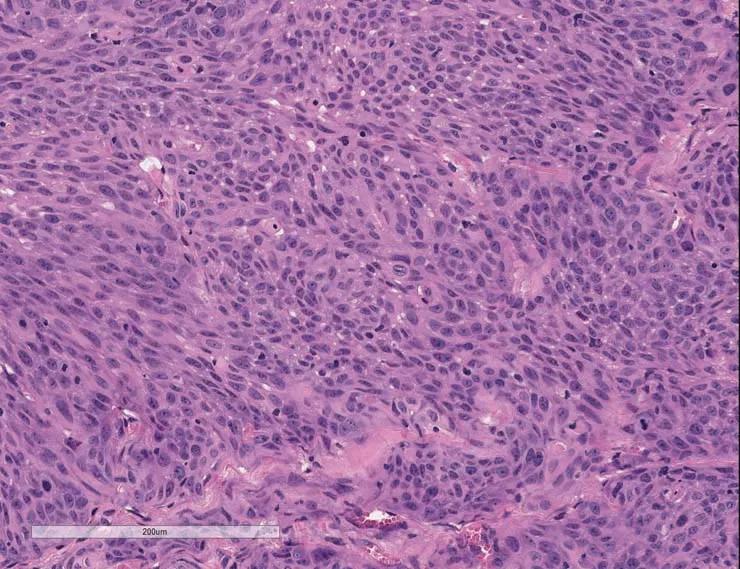

Low-passage samples retain the heterogeneity and fidelity of human cancers. Engrafted tumors derived from a patient with a bladder urothelial papillary carcinoma demonstrate high concordance of tumor morphology, compared to low passage PDX tumor TM00015.

Figure A) Histology from the patient's primary tumor: High-grade urothelial carcinoma invading the bladder wall.

Figure B) Once engrafted, the histology for PDX model TM00015 at passage 1 also corresponds to high-rate urothelial carcinoma.